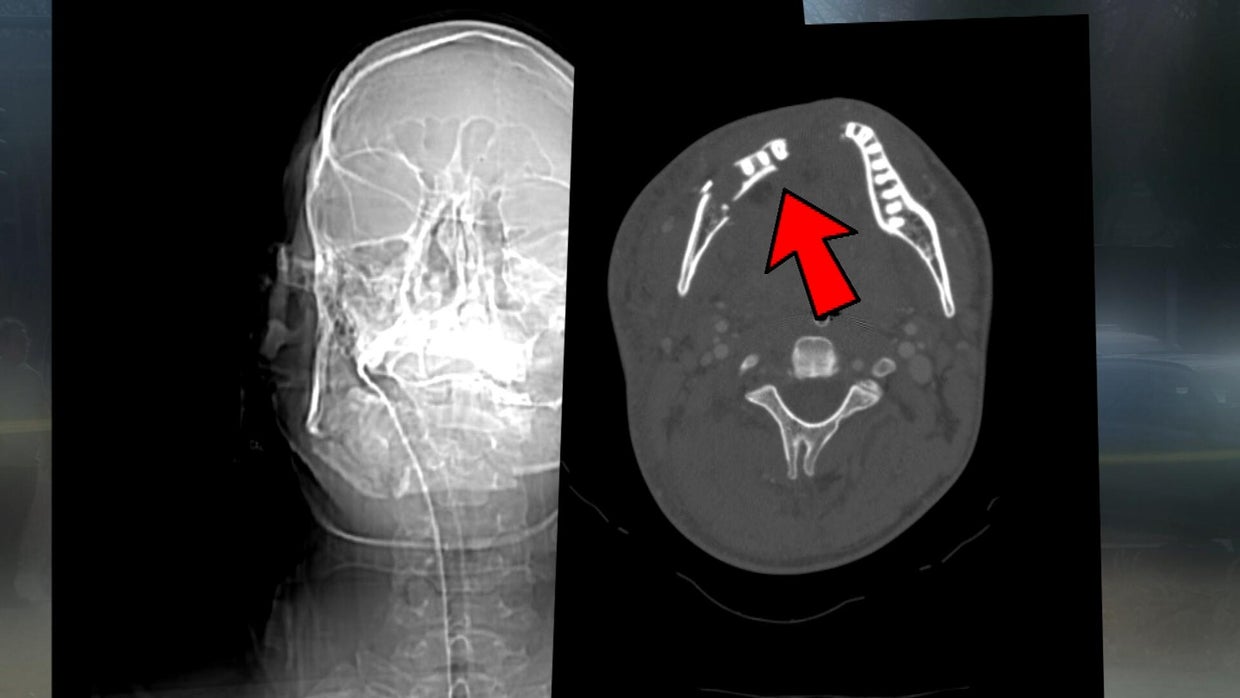

A bullet struck bystander Ben Varga, who was in the park to meet friends for a picnic. The bullet hit Varga in the back of the head and came out through his chin.

He suffered fractured vertebrae and is recovering.